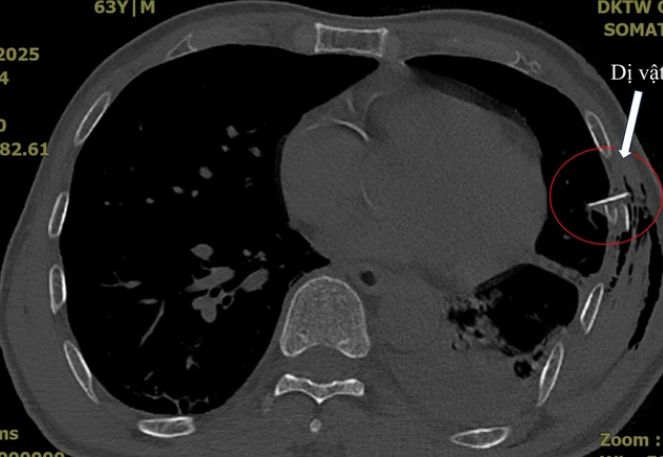

SKĐS - Ông V.Đ.Q (63 tuổi, trú xã Tam Hòa, huyện Núi Thành, tỉnh Quảng Nam) vào viện với tình trạng đau ngực sau chấn thương do tai nạn giao thông, bên ngoài hoàn toàn không có vết thương, chỉ có vết xây xước nhẹ ngoài da.